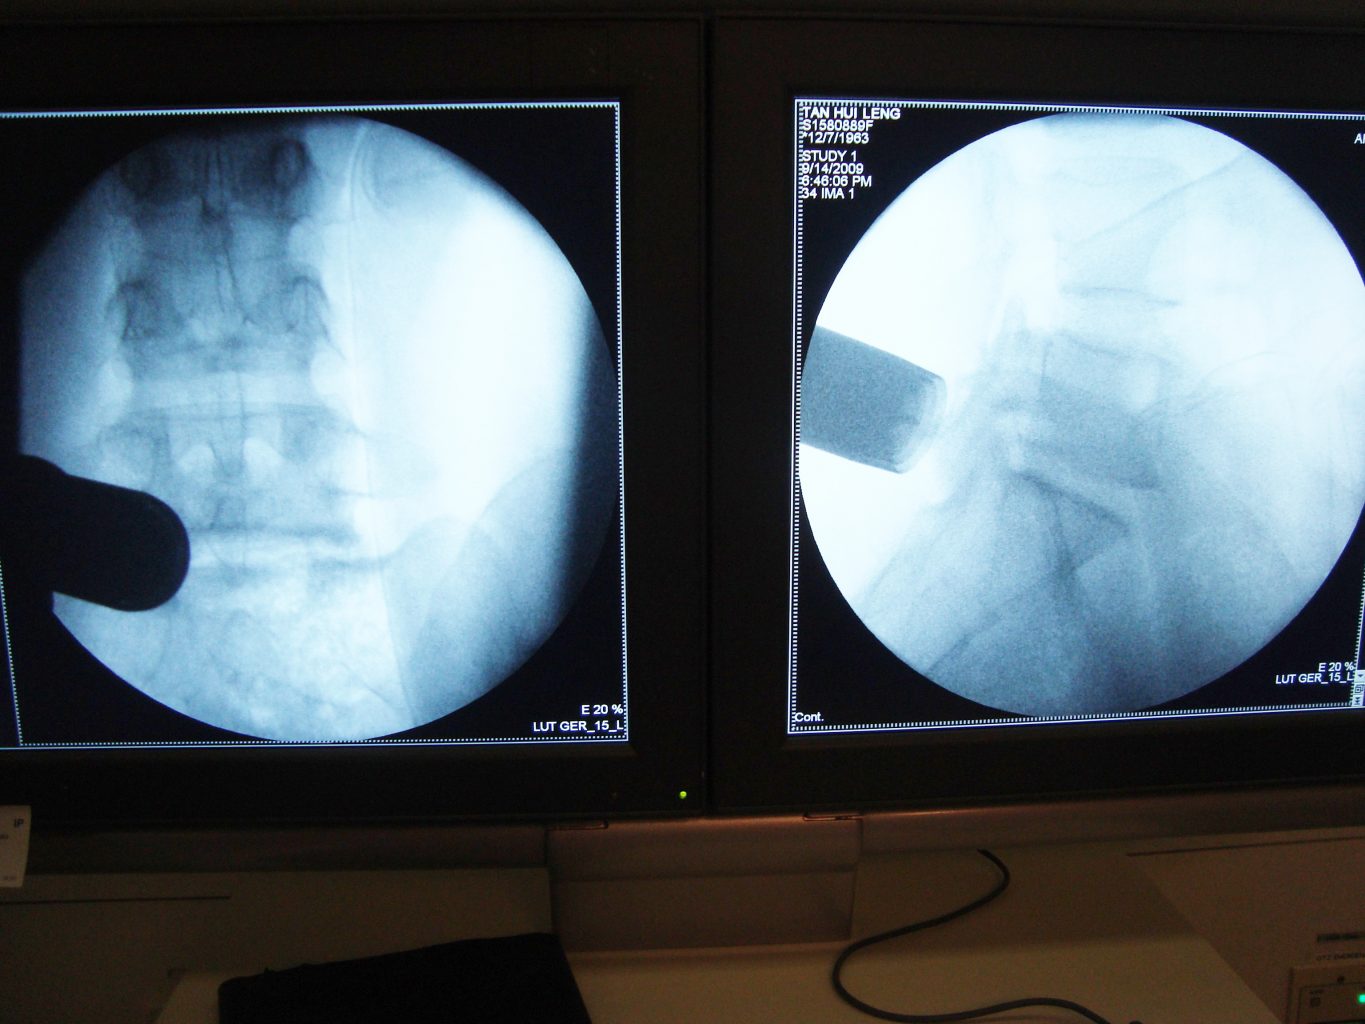

Active life style with Low Back Pain and Leg pain

Sciatica pain – Leg Pain Travelling to Calf and Back of Thigh with Numbness in whole leg

Difficulty in walking due to LEG PAIN